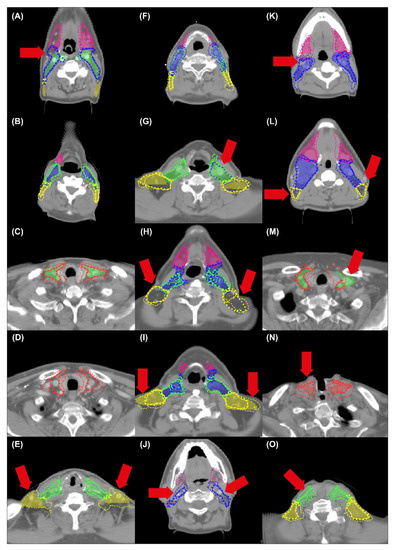

3. Results

4. Discussion